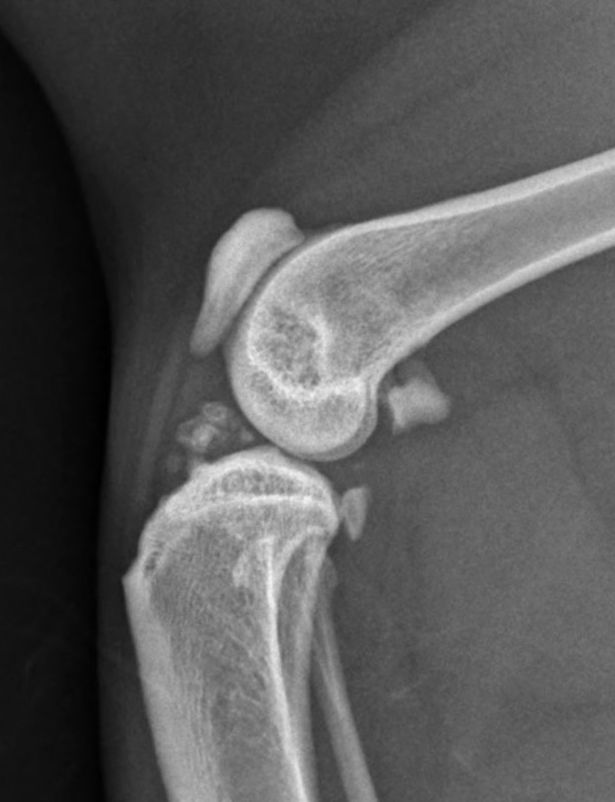

Radiografia

Apesar de suas limitações, a radiografia continua sendo o método mais utilizado para diagnosticar a osteosteoartritertrite em gatos, devido à sua ampla disponibilidade e percepção de custo-efetividade. No entanto, é amplamente reconhecido que a radiografia só é capaz de detectar osteoartrite em estágios avançados ou graves [16]. As características radiográficas observadas no diagnóstico da osteoartrite felina incluem a presença de osteófitos, aumento da opacidade do osso subcondral, mineralizações intra-articulares e de tecidos moles, espessamento dos tecidos moles e efusão sinovial (Figura 3). Quando alterações degenerativas são observadas nas radiografias, as mudanças degenerativas histológicas confirmam a presença de osteoartrite com alta especificidade [16].

No entanto, a radiografia é uma modalidade de imagem bidimensional, o que significa que alterações fora das estruturas esqueléticas ou próximas às bordas podem não ser facilmente visíveis [16]. Além disso, é impossível visualizar a cartilagem por meio de radiografias, e os achados radiográficos não estão bem correlacionados com a degeneração da cartilagem; um estudo constatou que até 71% das articulações femorais felinas com evidências macroscópicas de osteoartrite não apresentavam lesões associadas nas radiografias [17]. Essas limitações reduzem a eficácia da radiografia na detecção precoce ou leve da osteoartrite. De fato, um estudo recente observou que a radiografia não conseguiu detectar nenhuma articulação diagnosticada com osteoartrite leve histologicamente [16].

Apesar das limitações, a radiografia muitas vezes é a única modalidade de imagem disponível e, portanto, sua interpretação deve ser otimizada. Ter consciência de onde e do que procurar facilitará o diagnóstico precoce. O desenvolvimento de osteofitose pode ser mais lento em gatos do que em cães [2],[4], e outros sinais radiográficos, como diferentes tipos de formação óssea, podem ter uma relevância maior [17]. Embora os osteófitos sejam frequentemente considerados a principal característica radiográfica da osteoartrite, em felinos isso só parece ser verdade para a articulação coxofemoral [17],[18]. Para o cotovelo, tarso e joelho, as características radiográficas mais comuns são, na verdade, mineralizações associadas à articulação, proliferação óssea dorsal do tarso-metatarso e mineralizações intra-articulares, respectivamente [17]. Portanto, é essencial examinar minuciosamente as radiografias das articulações felinas em busca dessas outras formações ósseas ao redor das articulações e estar atento aos sinais de crescimento de osteófitos. Além disso, é fundamental lembrar das limitações da radiografia no diagnóstico precoce da osteoartrite. Quando há suspeita dessa condição, mas os sinais radiográficos não são evidentes, é importante buscar modalidades de diagnóstico mais sensíveis.

b

Figura 3. Imagens representativas demonstrando as alterações radiográficas comumente associadas à osteoartrite felina. Na visão ventrodorsal dos quadris (a), pode-se apreciar a formação de osteófitos nas margens acetabulares craniodorsais, além do remodelamento das cabeças femorais. Na visão mediolateral do cotovelo (b), pode-se apreciar um aumento da opacidade óssea subcondral na região peritrocilar, além da formação de osteófitos periarticulares. Na visão mediolateral do joelho (c), pode-se apreciar mineralização intra-articular e efusão sinovial. © Karen Perry